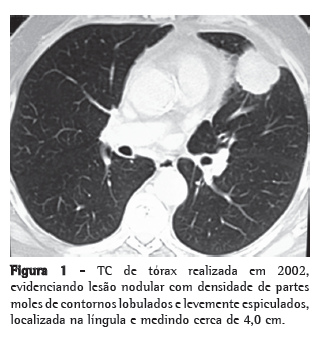

Paciente masculino de 71 anos de idade, com antecedente de lobectomia superior esquerda com ressecção do pericárdio por invasão local e linfadenectomia mediastinal há cinco anos (Figura 1). Estadiamento patológico IIB (T3N0M0). No seguimento com exame de imagem, achado de lesão pulmonar contralateral-0,8 cm no segmento superior do lobo inferior direito-não presente nos controles anteriores (Figura 2).